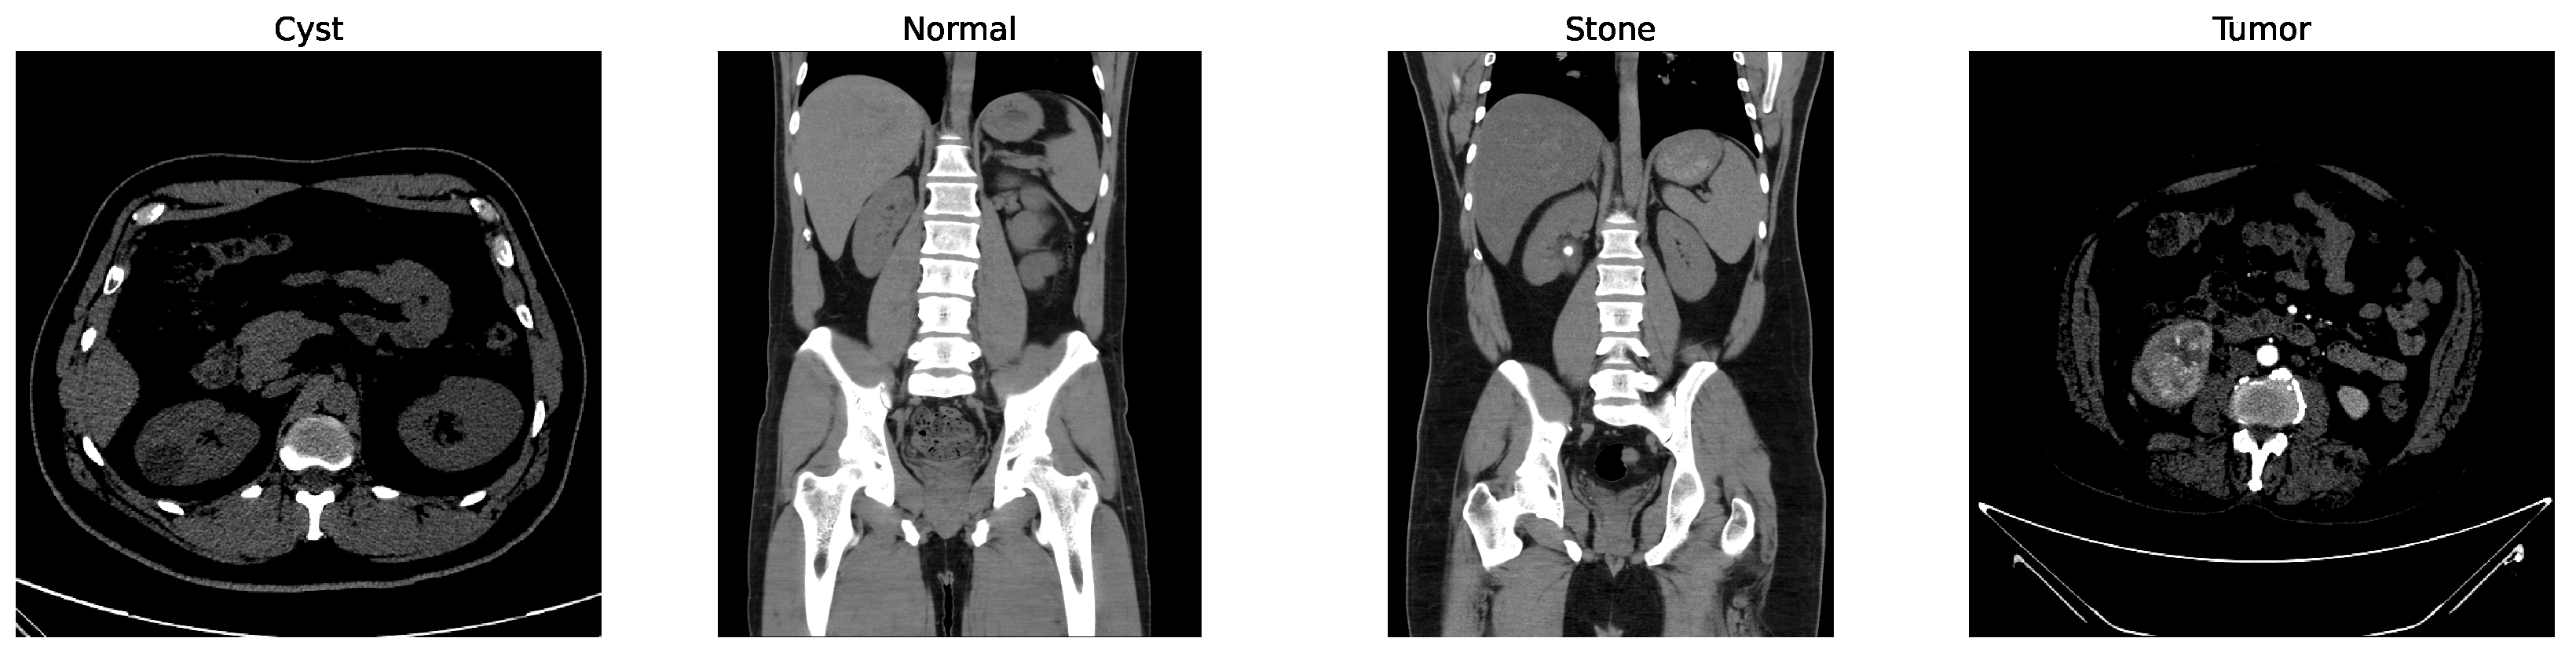

Some of the examples of the ct images of four classes are shown in Figure 3.

Figure 3.

Examples of cyst, normal, stone, and tumor CT image.

While other kidney diseases exist, this study specifically focuses on these four classes due to the availability and balance of labeled data in the dataset. Extension to additional diseases is left for future work.